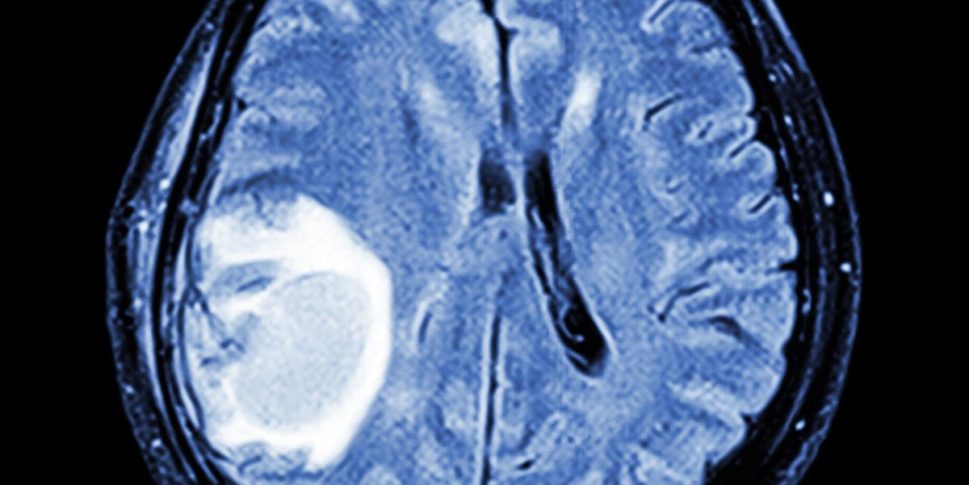

December 8, 2025December 8, 2025Cancer and tumour aren’t the same thing. Here’s the difference Featured by .Misusing the words cancer and tumour can be confusing and misleading Check your inbox or spam folder to confirm your subscription.